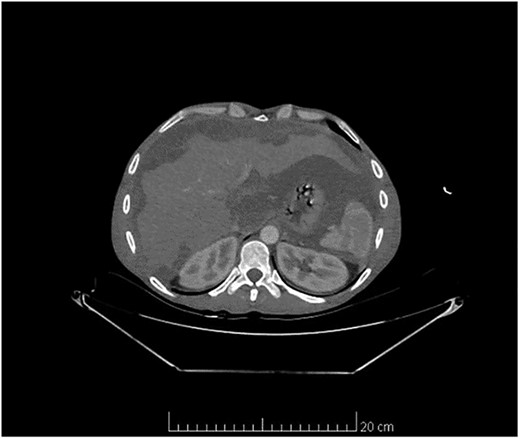

Laparoscopy showed severe adhesions and the abdomen cavity was full of mucus gelatinous fluid (Fig. 2). The rest of the abdominal cavities and appendix were not investigated due to the presence of severe adhesions and tuberculosis suspension.

Abdominal laparoscopy showed a huge amount of mucus gelatinous fluid.